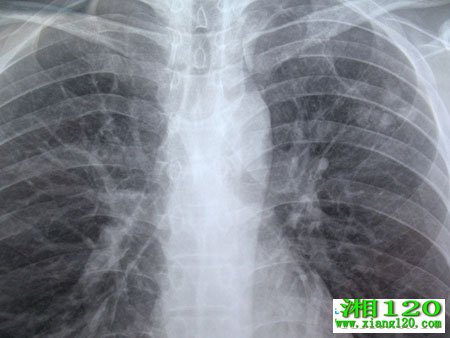

支气管内膜结核是结核病的一种特殊类型。近年来由于纤维支气管镜的广泛应用,使其确诊诊断明显提高。但临床上极少部分病人结核中毒症状并不明显,支气管内膜结核引起内膜增厚、管腔狭窄,症状和体征较易与支气管哮喘混淆。从而引起咳嗽、喘息、气急等哮喘症状为主要表现,造成了临床诊断困难。病人临床上较为少见,形成哮喘的机理是由于结核性肉芽组织增生,干酪样坏死物形成导致气管或支气管的狭流受阻而形成哮喘,因而容易误导临床医生诊断。,该类病人若误诊为哮喘,超生理量的糖皮质激素可抑制患者的非特异性免疫,为结核菌迅速生长繁殖并播散提供条件,结果导致肺结核的扩散,肺不张等严重不良后果,对哮喘患者(既往无支气管哮喘病史并排除其他常见病因),在经过抗炎解痉平喘等常规处理病情无明显好转者应考虑到该病的可能,并常规作纤维支气管镜检查,以明确诊断。